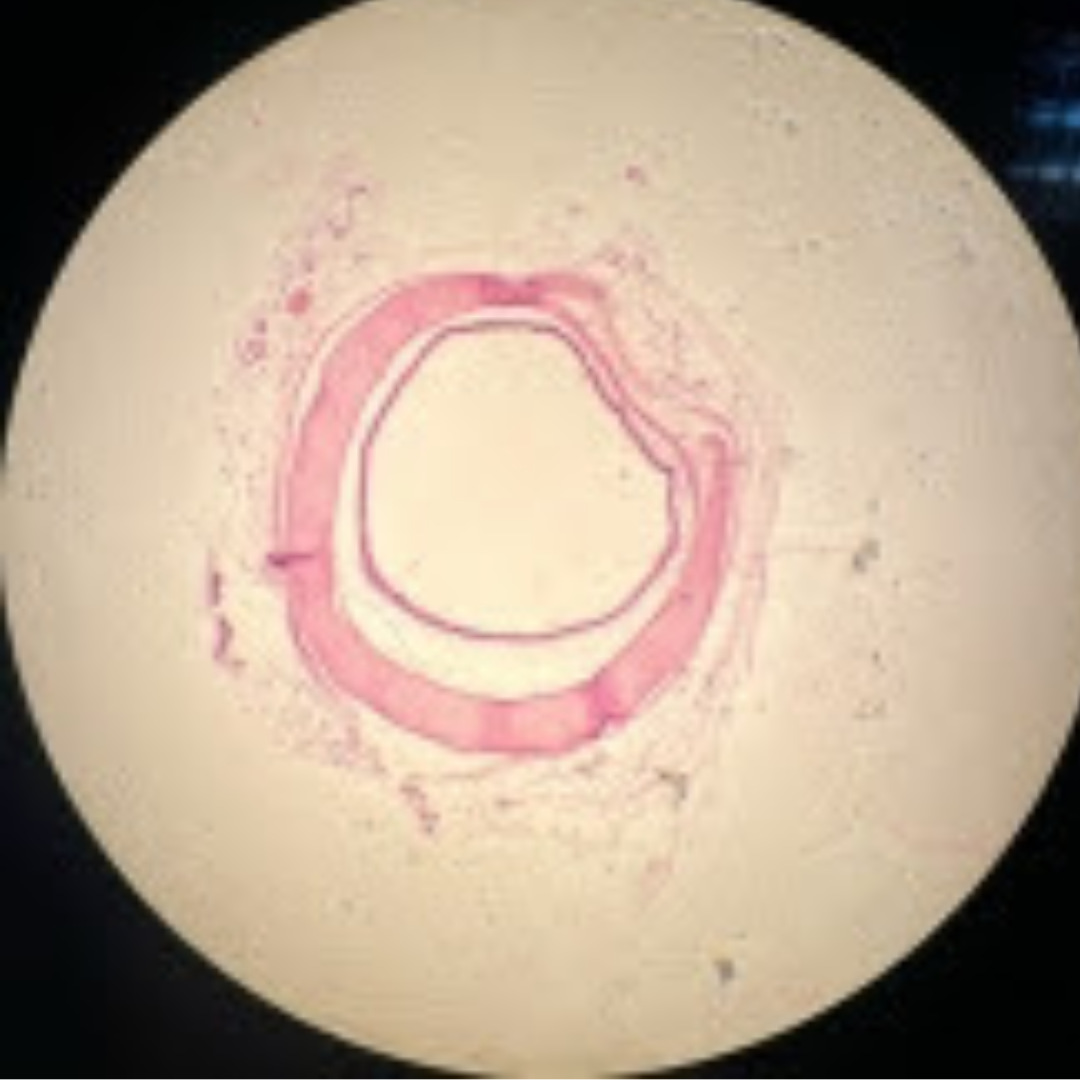

Lymphatic Vessel

Lymphatic Vessel

Lymphatic Vessel

Lymphatic Vessel

Lymphatic Vessel